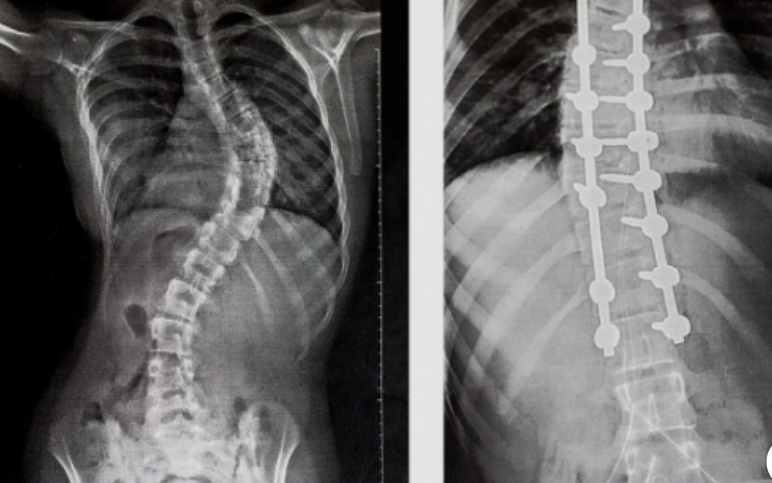

The road ahead was not easy. There were hospital visits, painful procedures, and long days of recovery that tested both her strength and mine. I watched her endure discomfort most adults would struggle to face—yet she met each day with determination, grace, and a smile that never faded. She didn’t ask, “Why me?” She simply kept going.

The day of her surgery is etched into my soul. As she was taken into the operating room, my breath caught in my chest. For eight long hours, time stood still. Every second felt endless. And then… she came out. Taller. Straighter. Stronger than ever before. 🏥🌈 In that moment, I didn’t just see my child—I saw a warrior who had fought bravely for her future.